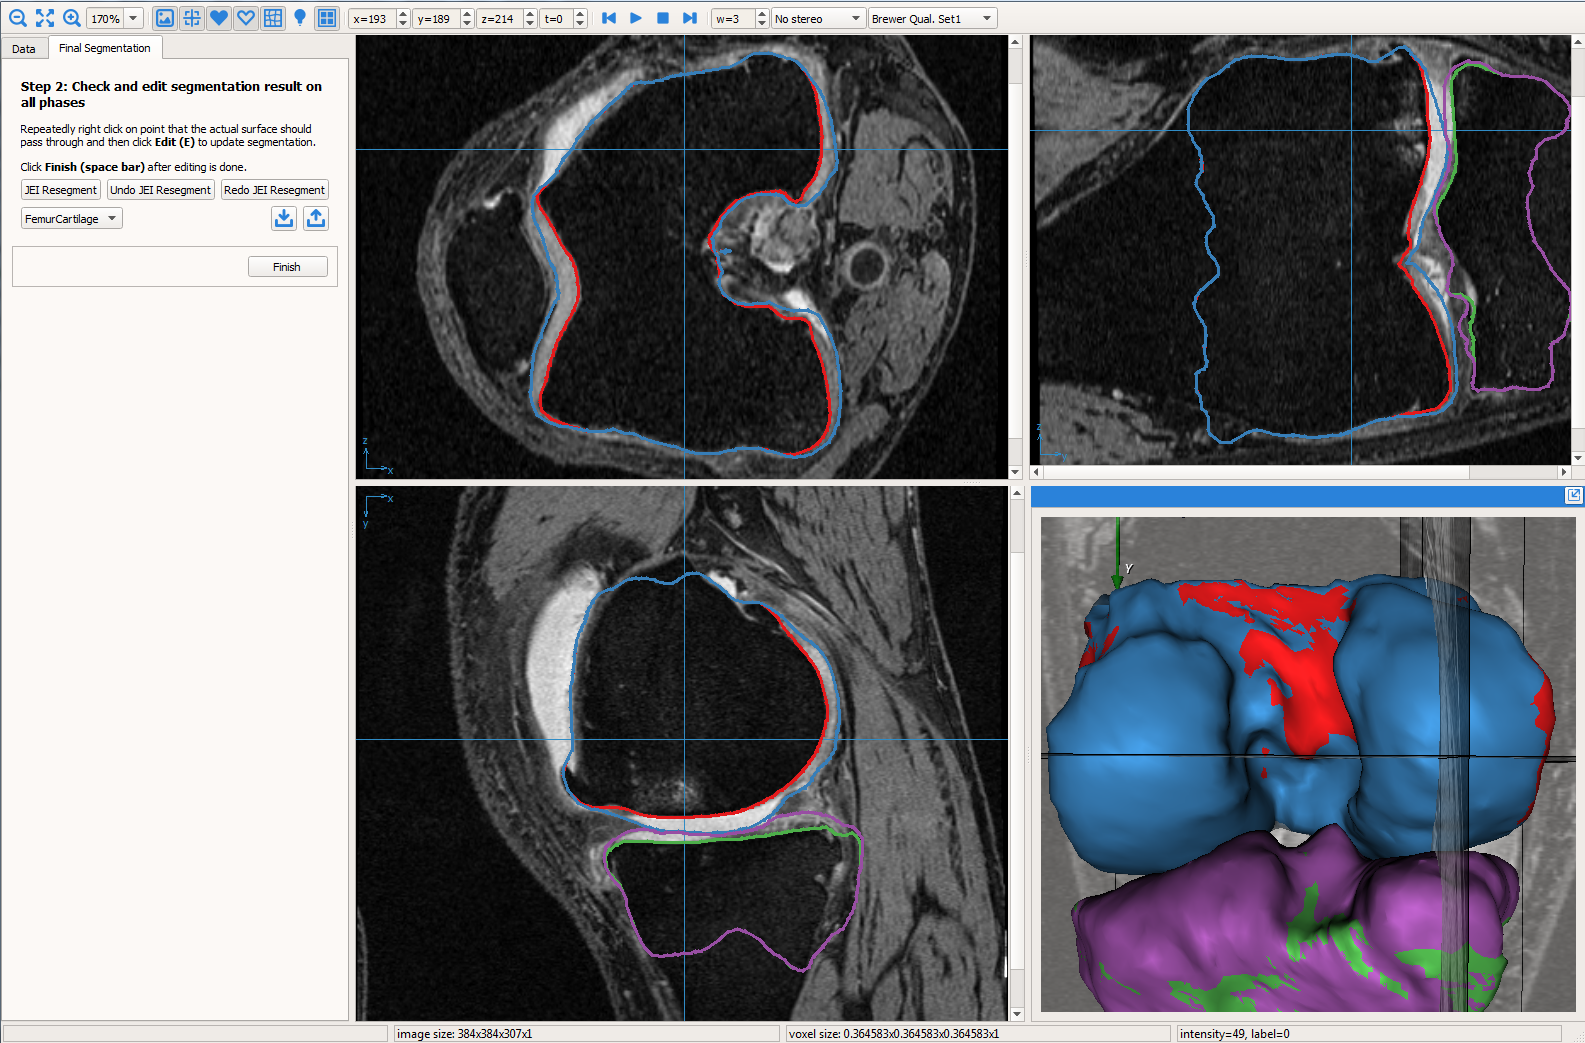

The electric lines of force (ELF) based geometric graph, image volume and residual graph were loaded into the GUI (see Fig. 1) to inspect segmentation quality and perform JEI. The work-flow is presented as a video provided in the supplementary material with an example subject with severe OA. The details of the work-flow were as follows:

User provided nudge points: The user identified correction is provided as a set of nudge points which guide the segmentation to the correct position. Fig. 3a shows the GUI magnified with the volume and the automated LOGISMOS segmentation results overlayed. The particular slice indicated is a case with severe OA having bright fluid regions improperly segmented as cartilage. The blue line with points are the nudge points indicated by the user approximately identifying the correct cartilage region.

Max-flow re-computation: Following the local graph cost modification the max-flow is recomputed in 3D within a few milliseconds and the updated surfaces rendered onto the GUI. As seen in Fig. 3b the correction made by the nudge points are reflected in the updated cartilage surface overlayed on the image volume.

The above work-flow is repeated to correct the tibial cartilage errors as well. In the intermediate steps following the correction of the femur, the tibia bone and cartilage surfaces appear to worsen. This can be attributed to a combination of the existing graph costs and the graph constraints. Since the tibia cartilage surface has no clear defined edge cost in that region, the surface result moved along with the femur corrected cartilage surface. Subsequently due to the inter-surface distance constraints between the tibial surfaces the tibial bone surface also changed. However once the nudge points provided the appropriate locations for cost modification the erroneous surfaces were corrected (Figs. 3c,d). Note that the corrections made on a single 2D slice resulted in the entire locally affected 3D neighborhood being corrected. This can be appreciated in the corresponding circled regions of the surface model.